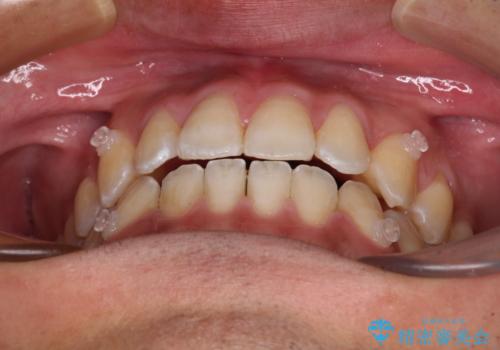

ワイヤー矯正を併用したインビザライン矯正治療

- 前歯のデコボコを気にして来院された患者様です。

歯列としてはワイヤー装置でもインビザラインでも対応可能でしたが、インビザラインが苦手とする上顎側切歯(真ん中から2番目の歯)の舌側転位が顕著でした。

治療の確実性を上げるために、インビザライン開始前に上顎のワイヤー装置にて舌側転位を解消し、その後インビザラインにて矯正治療を行うこととしました。

前歯のデコボコが早めに改善され、スムーズに治療を終えることができました。